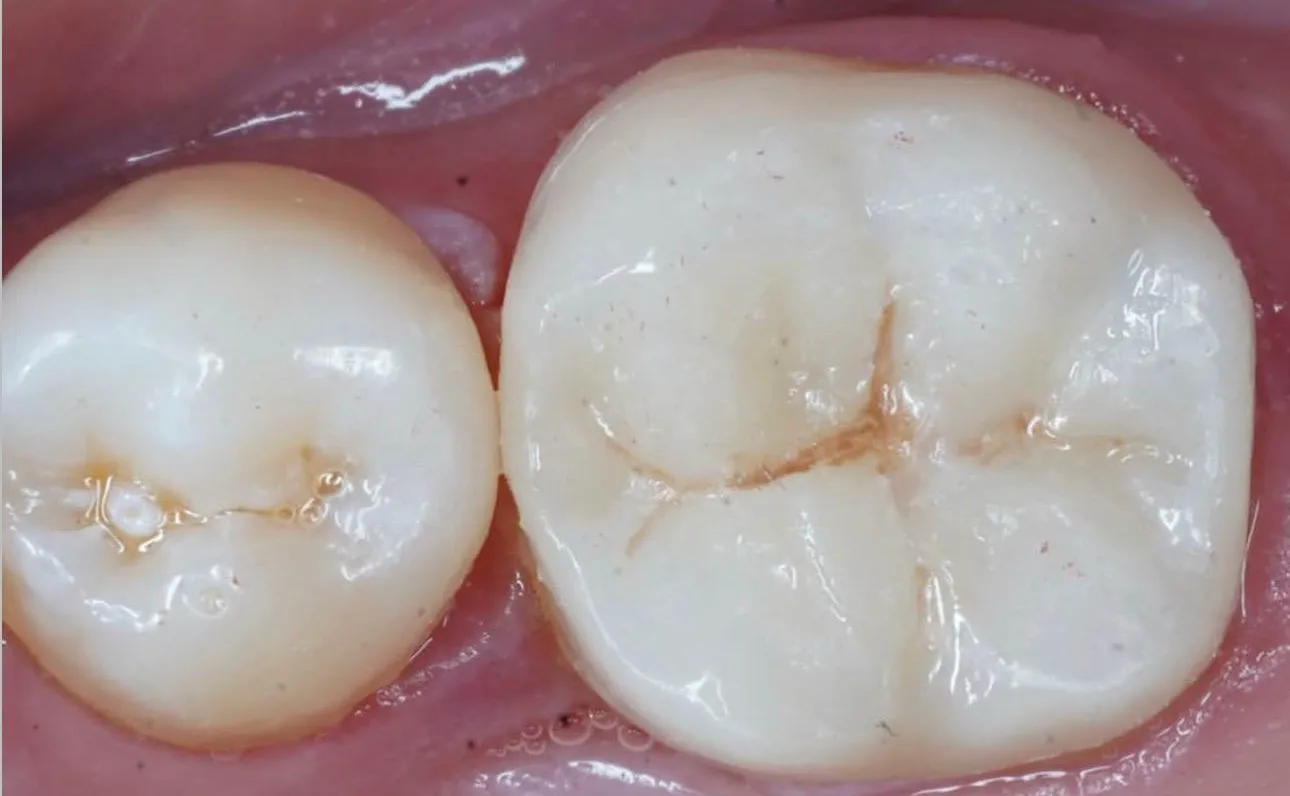

بعد